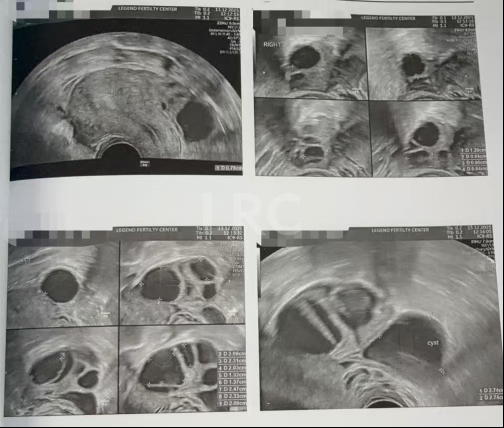

促排第八天

阴超检查:

- 右侧卵泡 4 颗 (11,10,9,8mm)

- 左侧卵泡 7 颗 (20,18,18,16,15,12,12mm)

激素水平检查:

- 促黄体生成素 3.50 miu/ml

- 雌二醇 959.9 pg/ml

子宫内膜厚度:6.4mm

促排第九天

- 右侧卵泡 3 颗 (13,11,10mm)

- 左侧卵泡 7 颗 (22,22,20,20,17,13,13,12mm)

子宫内膜厚度:7.8 mm